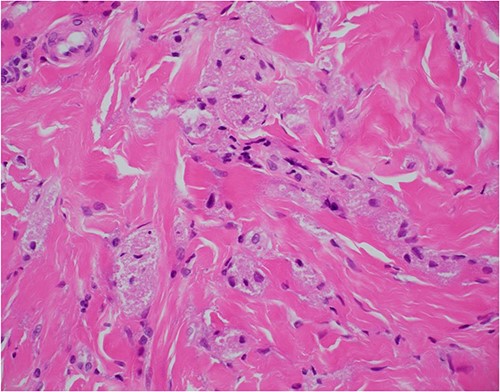

Haematoxylin and eosin stain, 400× magnification, showing tumour cell features of nests of epithelioid cells in the stroma with indistinct borders and granular pale eosinophilic cytoplasm.